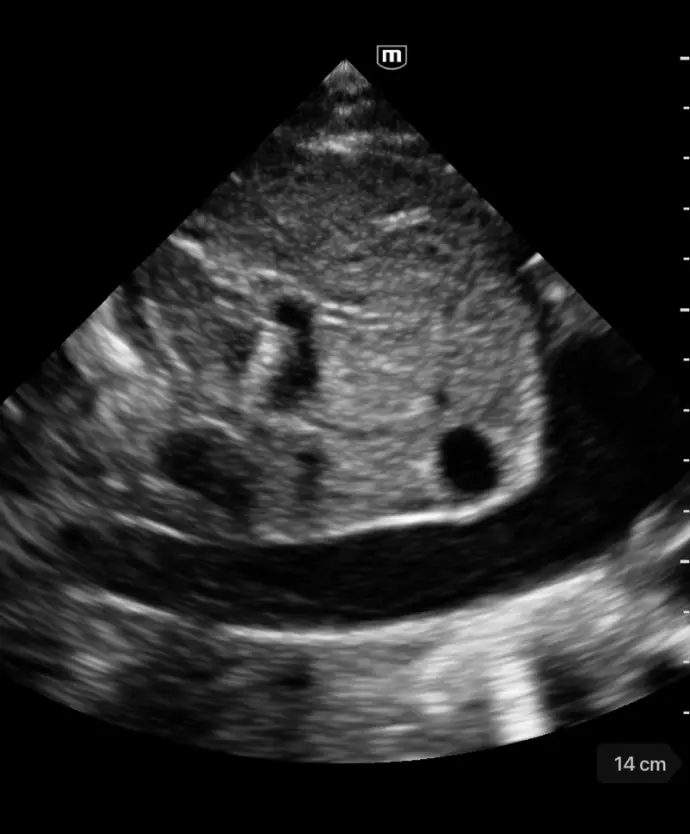

Клинични снимки

Чрез интегриране на множество приложения, TE Air e5M предлага сканиране на цялото тяло и се адаптира към различни клинични ситуации. Неговият безжичен дизайн осигурява възможност за извършване на ултразвукови изследвания с високо качество по всяко време и навсякъде. Освен своята универсалност, TE Air e5M предлага и редица интелигентни функции и обучителни инструменти, които повишават увереността и ефективността при работа.

Различни режими на визуализация: B-mode, M-mode, Color Doppler, Power Doppler, PW Doppler

FAST/eFAST, фокусирани сърдечни, коремни, транскраниални и основни белодробни

Бърза диагностика на сърдечната функция; скрининг за сърдечна патология